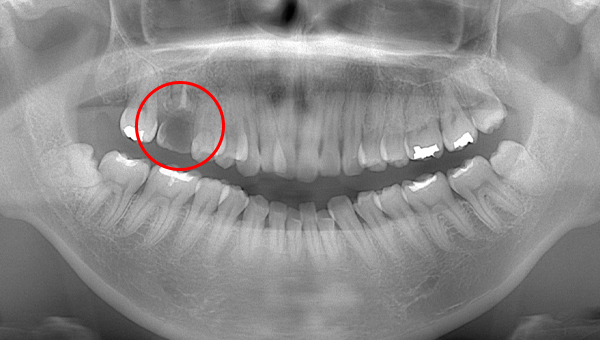

CT像①

CT像②

説明:

CT像です。根の中央を超えて虫歯が広がっているのがわかります。そこに上の親知らずを移植することに

しました。